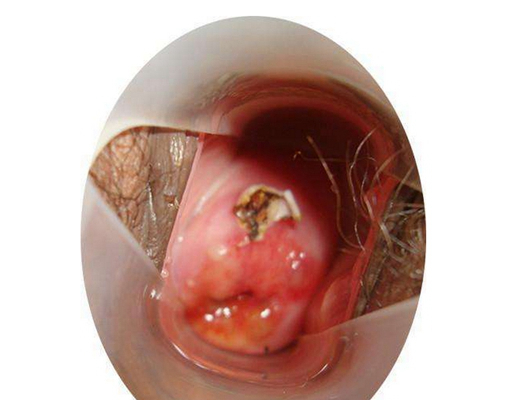

子宮頸糜爛圖片

宮頸糜爛 (8)

宮頸糜爛 (9)

宮頸糜爛 (56)

宮頸糜爛 (57)

宮頸糜爛 (58)

宮頸糜爛 (59)

宮頸糜爛 (6)

宮頸糜爛 (60)

宮頸糜爛 (7)